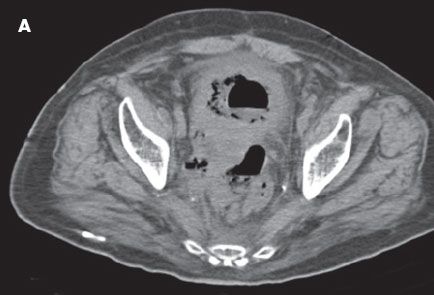

CT scans of the abdomen and pelvis showed a large prostatic mass without delineation between the prostate, rectum, and bladder. A fistula was noted between the rectum and bladder (A, B, and C). Copious subcutaneous gas was visible in the perineum and in all 3 corpora of the penis (D). Blood cultures were positive for Clostridium perfringens. Necrotizing fasciitis was diagnosed, and the patient underwent a loop colostomy.